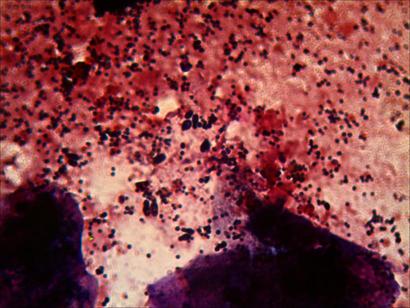

Vamos al tema, la muestra es de un canario que pierde plumas y por lo que veo tiene una infeccion de malassezia, a la que se le ha agragado una invasión de estafilococos.

Ahora vamos a las fotos……las manchas grandes de tonos rosados y violaceos, son escamas,restos de piel en las que a veces se observan algunas celulas deterioradas bastante bien…..en la primera foto vemos, los puntos negros son cocos, que estan haciendo las clasicas agrupaciones en racimo de los estafilococos…..en la parte central izquierda, podemos ver un grupo de levaduras de malassezia((hongos))….estas se distinguen de las bacterias, principalmente por su forma ahuevada y su tamaño superior, y en algunos casos las vemos en proceso de gemacion((reproduciendose)).

La segunda foto, son básicamente levaduras, tanto la mancha oscura y poco clara de la parte superior como la de la paret inferior.

En la tercera vemos un popurri mucha bacteria y algunas levaduras, y la cuarta son todo levaduras.